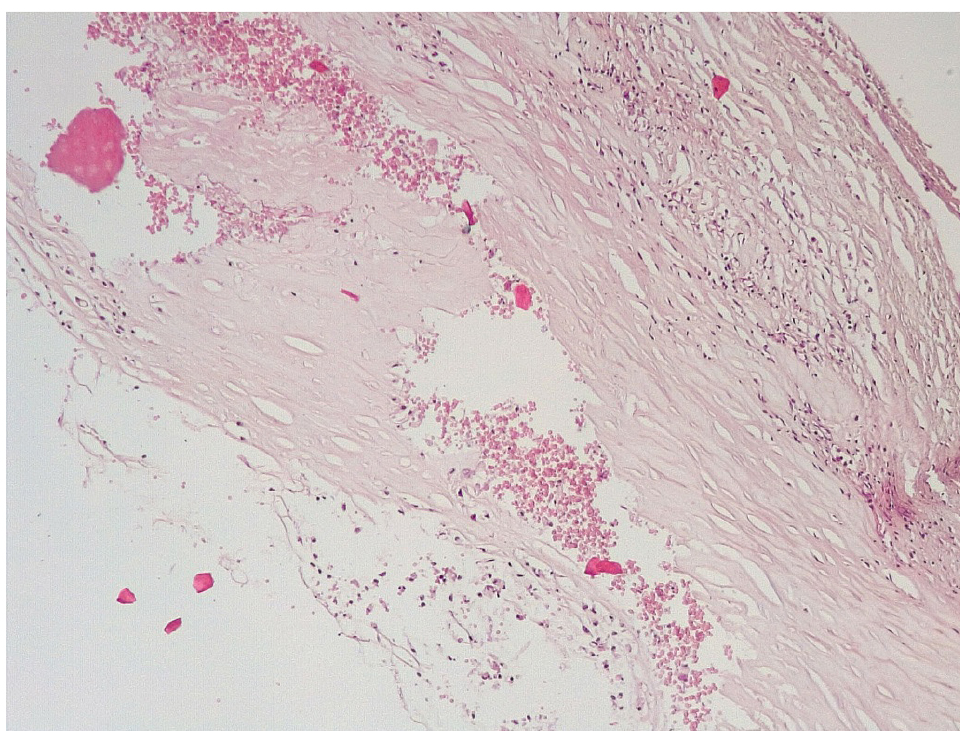

В течение 7–15 суток после стентирования КА наряду с формированием пристеночных фибриновых тромбов с признаками организации в стенках атером наблюдались репаративные процессы, связанные с неоангиогенезом в виде образования мелких тонкостенных кровеносных сосудов капиллярного типа, окруженных мелкими лимфоцитарными, гистиоцитарными клеточными инфильтратами (рис. 6, 7).

Сохранялась резковыраженная яркая экспрессия ФВ как со стороны интимы, так и субинтимально, в участках альтерации атером (рис. 8). В то же время экспрессия белка CD31 была негативной на всем протяжении стенок КА.